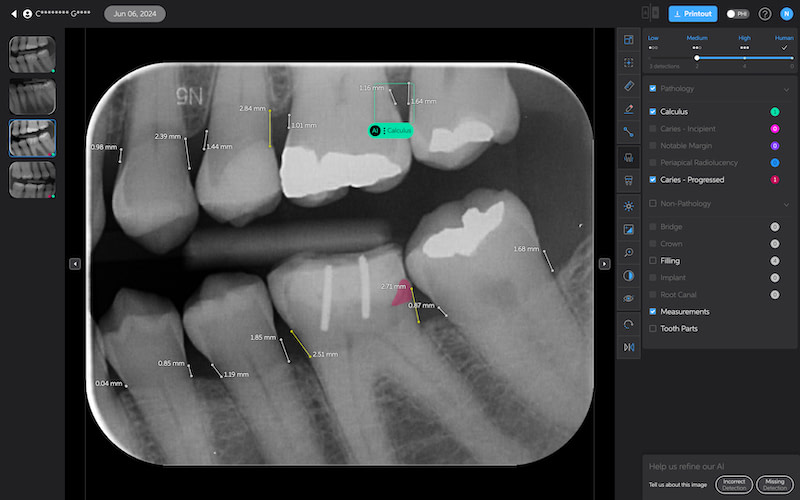

Calculus Detection

Green squares highlight areas of radiographic calculus. This tool is useful for hygienists and dentists in treatment planning and patient education.

Quite self-explanatory and the system didn't seem to miss often, if ever.

Caries Detection

The best for last and arguably the most well-thought-out feature. Especially with the tooth segmentation mode, which makes it easier for patients to understand their diagnosis and treatment plans.

The system uses two shades of pink to indicate potential caries:

- Light pink: Incipient caries (100% in enamel) - we will often review

- Darker magenta: Caries extending into dentin - we need to restore

The system even provides a percentage breakdown of enamel vs. dentin involvement. I have been blown away by its accuracy while using it, and it makes something that feels quite subjective (reading shades of grey) into a science.

This feature is very useful for patient education and deciding between preventive measures and restorative treatment. However, remember that radiographic evidence alone is not always sufficient for a definitive caries diagnosis.